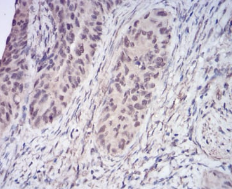

IHC    1/200 - 1/1000